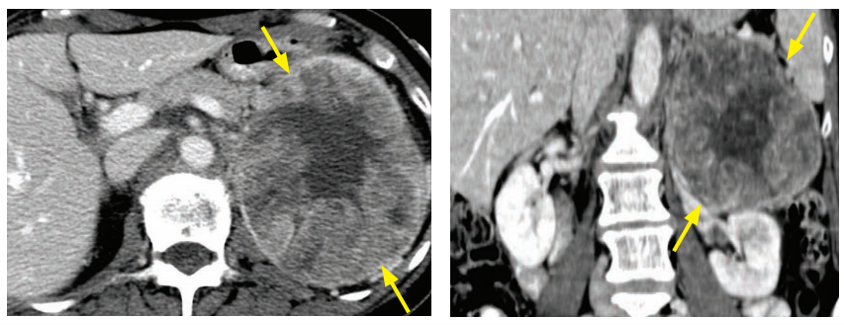

adrenal myelolipoma

presacral myelolipoma